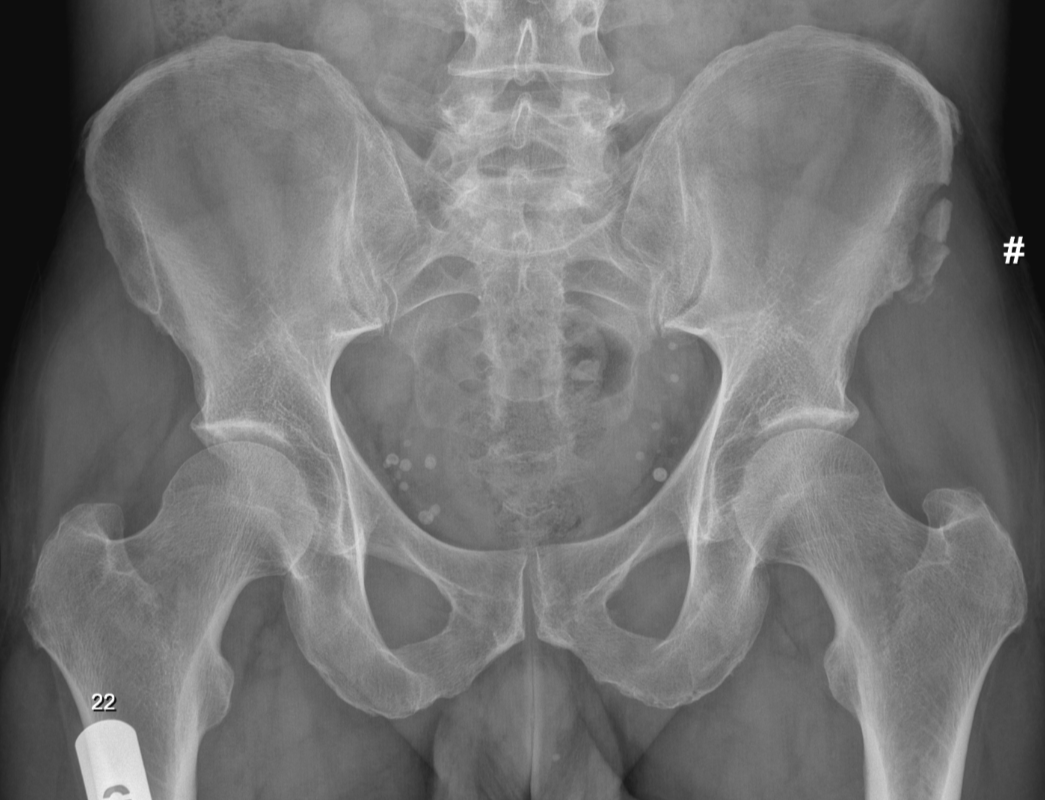

3. Sartorius avulsion injury